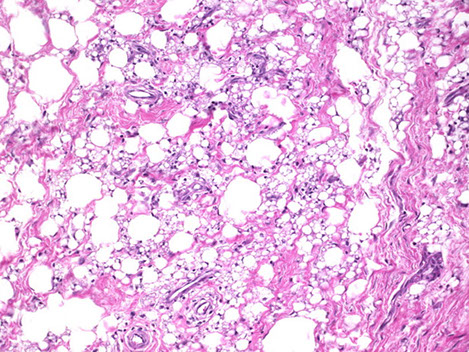

Aggressive Angiomyxoma

Mostly in perineal and pelvic regions of women

Micro: Circumscribed and has peripheral infiltrative margins c extension into adjacent structures

- hypocellular c monotonous small spindled and stellate fibroblastic cells in background of myxoid stroma and prominent, dilated, thick-walled vessels

IHC: (+) CD34 (usually do not need IHC), HMGA2 (sens but not spec, good for evaluating margins in re-excision specimens)